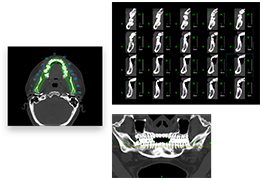

工作流智能。

在这里,先进的智能功能自动执行手动任务和工作流程步骤,以简化流程,提高技术人员工作效率,节省时间和金钱,并增强患者护理。

自动化设备定位和患者姿势确认可优化放射科技师的效率并加快工作流程。

自动技术选择可改善影像一致性并支持辐射剂量控制。

通过任务自动化功能改进感染控制,使放射科技师不再与潜在感染患者直接接触。